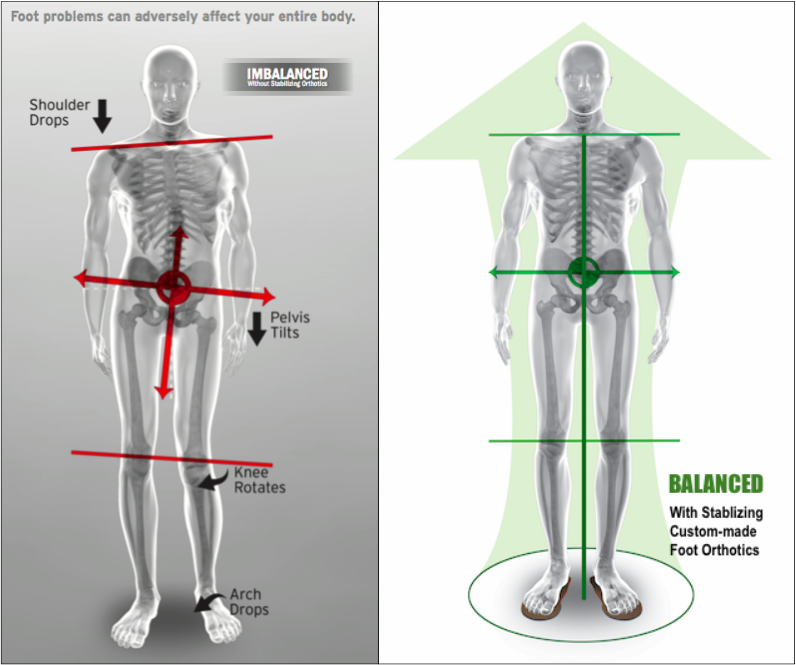

Chronic knee, hip and back pain

Flat feet is not the norm and are usually caused by a lack of tendon support in the arches of the feet. However, this condition can cause pain in various other parts of the body, including the back, hips, and knees.

Flat feet also don’t have a proper arch to absorb the shock of everyday walking, running, standing, etc. This means that your joints – especially the knees and hips - have to absorb all this shock, even though they aren’t designed to do so. Over time, this added stress can cause severe ankle, knee, hip malfunction, and chronic low back and neck pain.